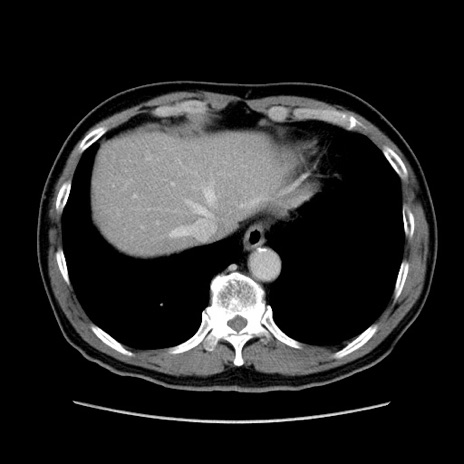

【症例】60歳代 男性

【主訴】右鼠径部膨隆

【現病歴】1年程前より右鼠径部膨隆あり。自己にて還納可能だったため放置していた。3時間前より右鼠径部の脱出を認め、還納困難となり受診。

【身体所見】右鼠径部に小児頭大の膨隆あり。弾性硬であり、用手還納は困難。左鼠径部にも膨隆を認める。脱出はなし。